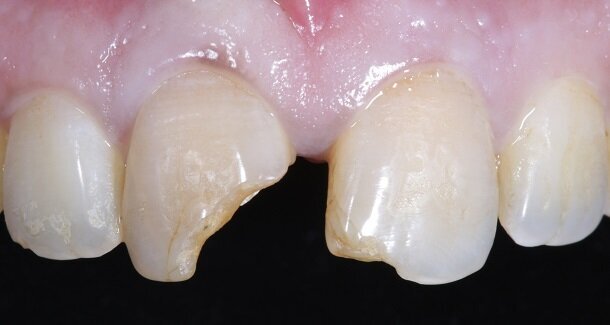

Presenting a case of a 22 yr old male, who reported to our dental office with fractured Maxillary Central incisors many years ago [Figures 1 and 2]. On examination both Maxillary Central incisors had fractures with pulp exposures. IOPAR showed large peri-apical lesions in both teeth. There was no mobility seen in either teeth, but discolouration was seen in both. Non-surgical Endodontic treatment followed by Bleaching and Direct composite restorations (2 weeks post bleaching) were planned.

The figures show the clinical work flow involved. In the 1st appointment Oral prophylaxis, oral hygiene instructions were followed by an impression that was sent to the lab for a wax up [Fig 3 and 4]. In the subsequent appointments, Endodontic treatment was followed by Intra and extra coronal office bleaching using the Pola office bleaching kit. After two weeks, the shade stabilised post bleaching. Shade selection, rubber dam isolation and preparation was done on both the teeth to receive Direct composite veneers so as to close the midline diastema as well as correct the fractured teeth and the slight mal-alignment. Controlled Body Thickness (CBT) technique of layering was used with 3M Z350XT shades - Dentin shades A3, A2 and Enamel shades A2, clear translucent [Figures 5 to 11]. This was followed by the Finishing and polishing protocol as described in the figures.